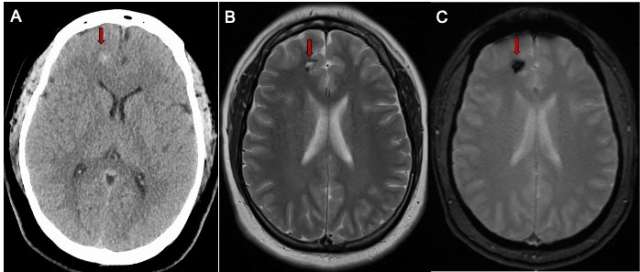

Whether the CCM has caused bleeding or not, the following advanced imaging (Figure 1) techniques may be used to diagnose it:

• Magnetic resonance imaging (MRI) scan can help locate the CCM and the area of affected brain or spinal cord.

• Computed tomography (CT) scan can assess any bleeding into the brain tissue.

CT scan of the brain

Figure 1. Cerebral Cavernous Malformation Imaging - CT scan of the brain (A) in a patient with a mild headache showing a small spot of white bleeding (red arrow). B) A brain MRI scan T2 sequence demonstrating a small cavernous malformation (red arrow)